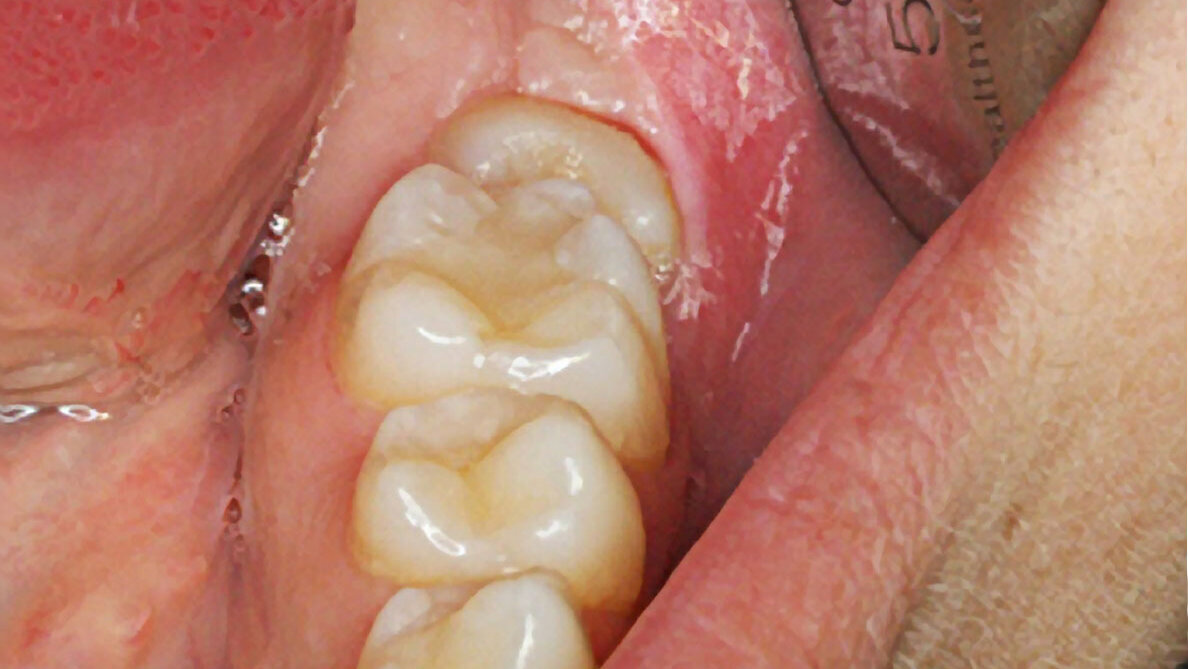

Fotografía clínica de final de tracción.

Fotografía intraoral lateral (tubos cementado directo en 6 y 7).

Fotografía clínica final.